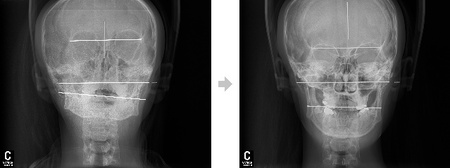

- 안면비대칭 수술 없이 치료할 수 있을까?

- 최근 외모에 대한 관심이 높아지면서 성형수술을 하는 환자들이 늘어나고 있다. 특히 얼굴형에 대한 관심이 많아지면서 양악수술을 받고 있는 환자들이 ...